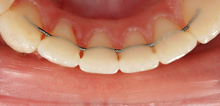

Health and Success − Aesthetics and Function